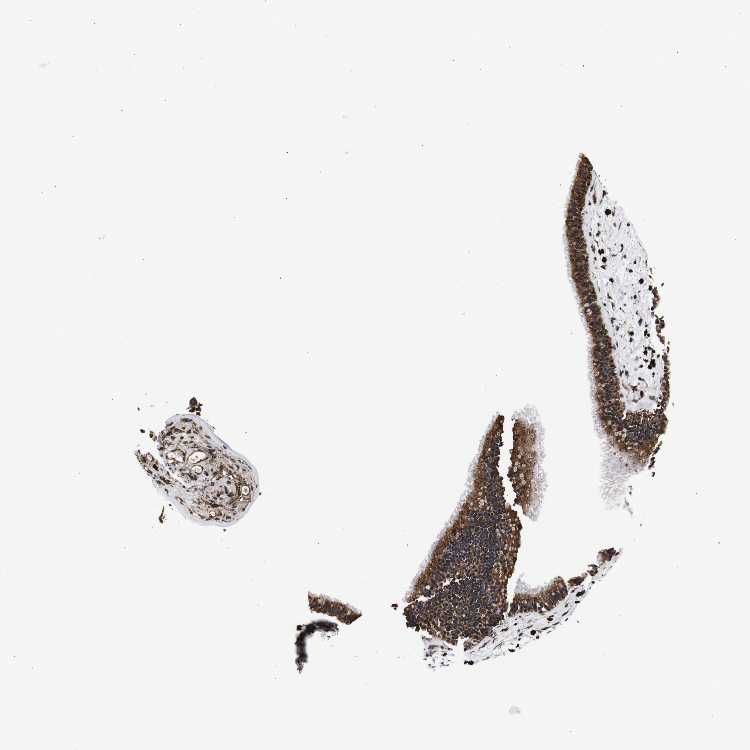

NASOPHARYNX - Antibody stainingi

Antibody staining in the annotated cell types in the current human tissue is reported as not detected, low, medium, or high, based on conventional immunohistochemistry profiling in selected tissues. This score is based on the combination of the staining intensity and fraction of stained cells.

Each image is clickable and will lead to virtual microscopy that enables deeper exploration of all samples and also displays staining intensity scores, fraction scores and subcellular localization as well as patient and tissue information for each sample.

Antibody HPA012616

Respiratory epithelial cells High